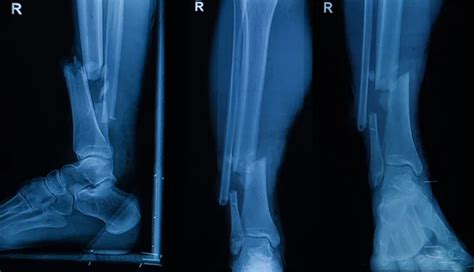

Alright, let’s start with the basics, shall we? What is a depressed fracture ? Imagine you take a ball and hit a delicate object – it doesn’t just shatter; sometimes, a piece gets pushed inward . That’s essentially what happens with a depressed fracture in a bone. Instead of the bone breaking and fragments sticking out (like an open fracture) or the bone simply cracking, a depressed fracture involves a portion of the bone being pushed below the normal surface of the bone. This is most commonly seen in bones that have a relatively flat, thin structure, like the skull. A severe impact, like from a car accident, a fall, or a direct blow to the head, can cause a piece of the skull to cave inward. It’s pretty serious stuff, guys, because that inward displacement can put pressure on underlying structures, like the brain. It’s different from a simple contusion or bruise, and it’s definitely not the same as a hairline fracture. The key here is the depression or inward displacement of the bone fragment. Sometimes, these fractures can be open, meaning the skin is broken, and sometimes they’re closed, where the skin remains intact. But the defining characteristic is that inward dent. It’s a significant injury that often requires immediate medical attention, not just because of the break itself, but because of the potential complications arising from the displacement. We’re talking about potential neurological damage with skull fractures, or internal bleeding. It’s a serious mechanical failure of the bone structure, and understanding this physical characteristic is the first step before we even think about coding it.